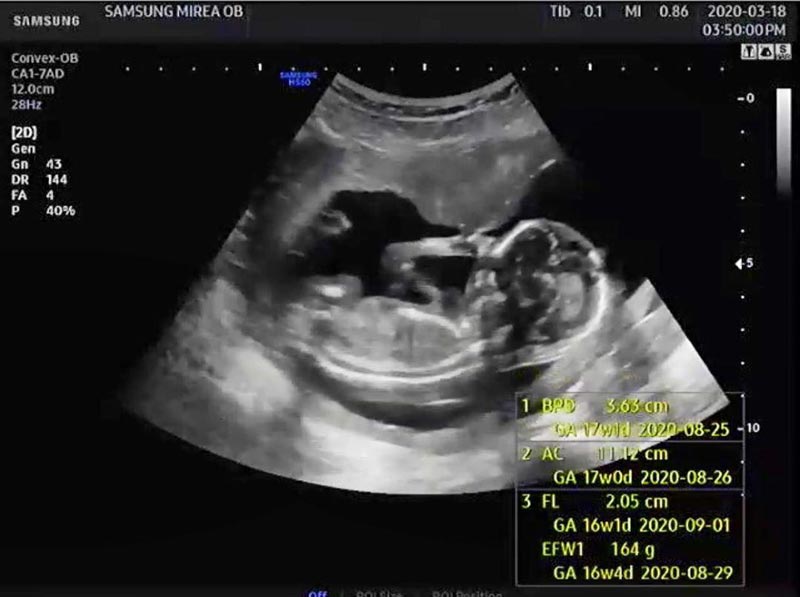

ภาพจาก Instagram auan_rangsit

เรียกว่าแฟน ๆ และเพื่อนในวงการบันเทิงต่างรอลุ้น และส่งกำลังใจให้อย่างเนืองแน่น หลังจากที่ อ้วน รังสิต ได้เปิดเผยข่าวดีว่าในวันนี้ (17 สิงหาคม 2563) ภรรยาสาวชาวเกาหลีใต้ มะม่วง หรือ ปาร์คฮยอนซอน ได้เข้าห้องผ่าตัดเตรียมคลอดลูกคนแรกแล้ว

ล่าสุด อ้วน รังสิต เผยคลิปวิดีโอของภรรยา ที่มาเล่าความรู้สึกหลังจากผ่าคลอด ระบุว่า ตอนผ่าตัดไม่รู้สึกอะไร เพราะว่าฉีดยาชา ซึ่งคุณหมอก็พูดคุยดี รู้สึกอบอุ่น ทำให้อยู่ดี ๆ ก็ร้องไห้ออกมา ยิ่งตอนที่หมอเอาลูกออกมาก็ยิ่งรู้สึกประหลาดใจว่าในท้องมีอีกหนึ่งชีวิตอยู่จริง ๆ

พอลูกออกมา คุณหมอก็อุ้มมาให้ดู ยิ่งทำให้มะม่วงร้องไห้หนักขึ้นไปอีก เพราะลูกน่ารักมาก บวกกับหลากหลายความรู้สึกที่ประดังประเดเข้ามา ทั้งดีใจ ตกใจ ประหลาดใจ ที่ตัวเองกำลังจะกลายเป็นแม่คนแล้ว